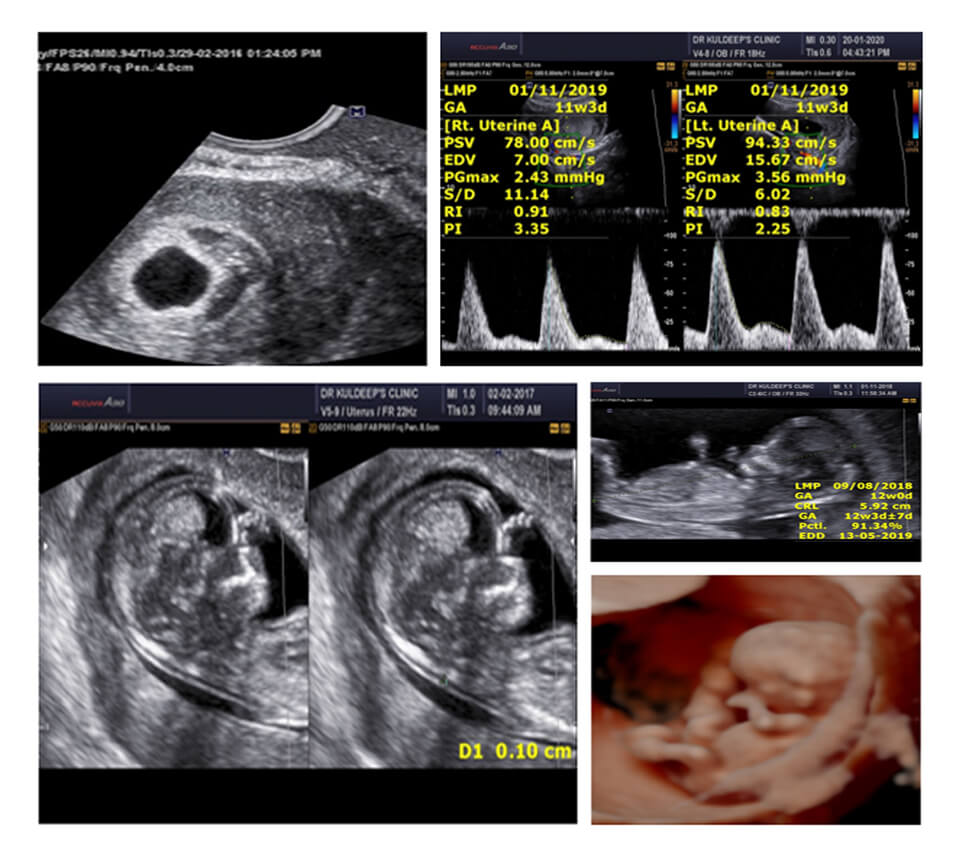

FIRST TRIMESTER (11-14 WEEKS) USG

WEEK 1 SCREENING : STRATEGY AND APPROACH

WEEK 2 NT SCAN: THE CORRECT APPROACH

WEEK 3 NB/ICT ASSIGNMENT SUBMISSION

WEEK 4 DV/TR/UTERINE ARTERIES ASSIGNMENT SUBMISSION

WEEK 5 STRUCTURAL SCAN REVISION & ASSIGNMENT SUBMISSION

WEEK 1

LEARN THE CONCEPTS OF BIOCHEMICAL SCREENING

UNDERSTAND STRATEGIES OF SCREENING

APPRECIATE AND LEARN LOW, INTERMEDIATE AND HIGH RISK

LEARN ABOUT THE BEST SCREENING MODALITIES

WEEK 2

LEARN THE CORRECT MAGNIFICATION

WHAT DOES A THICK NT MEAN

WHAT AFTER A THICK NT

WHAT ALL TO SCREEN FOR WITH A THICK NT

LEARN THE CORRECT TECHNIQUE FOR DV/TR

WHAT DOES ABSENT A WAVE MEAN

WHEN DO YOU CALL IT TR

WHAT AFTER AN ABNORMAL DV/TR

PREECLAMPSIA SCREENING

MEAN UTPI CALCULATIONS